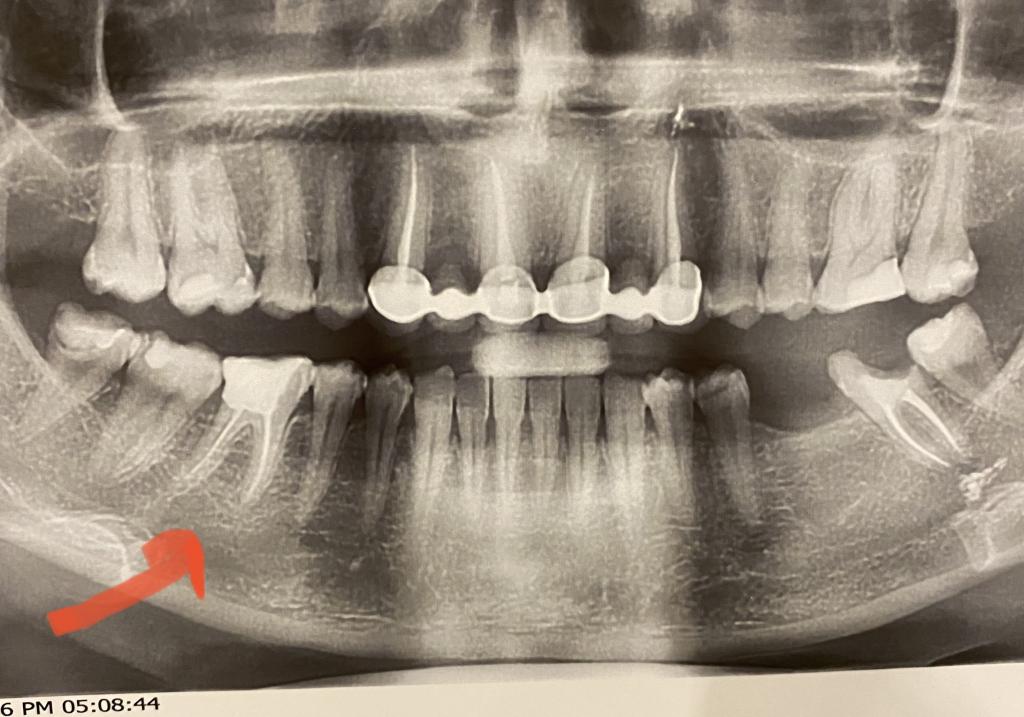

Добрый вечер. 46 зуб учитывая то, что он мертвый и без коронки, то, что Вы жуете только на правую сторону достаточно много времени - скорее всего трещина корня. На снимке зачастую ее не видно. Также не исключается вариант неплотной обтурации дистального канала - на снимке есть просвет между обтурирующим материалом и стенкой канала. Третья причина болей может заключаться в полости под пломбой восьмого зуба справа внизу. Зачастую боли иррадиируют от проблемных зубов мудрости, заставляя пациента думать, что болит другой зуб. Поиск причины затягивается, начинают лечить все подряд, пока доктор, к которому нельзя попадать, не удалит причинный зуб мудрости.

Слева семерку нужно восстанавливать и покрывать коронкой в составе моста 35-37 предварительно удалив зуб мудрости слева внизу.

Он не позволит мосту нормально сесть, из - за своего наклона в сторону семерки. Для нормальной посадки его нужно подпилить.

Вариант второй - просто коронка на 37 и имплантат 36. В этом случае 35 останется нетронутым.

Будете делать мост на 35-37, ни в коем случае не депульпируйте его (не убивайте нерв).

Результат убийства зубов Вы можете наблюдать у себя на верхней челюсти. Для восстановления двух маленьких боковых резцов Вам "специалисты" высверлили зубы изнутри, выдернули нервы из четырех зубов, опилили их снаружи так, что мост отклеился, потому, что от зубов мало что осталось и сила сцепления минимальна.